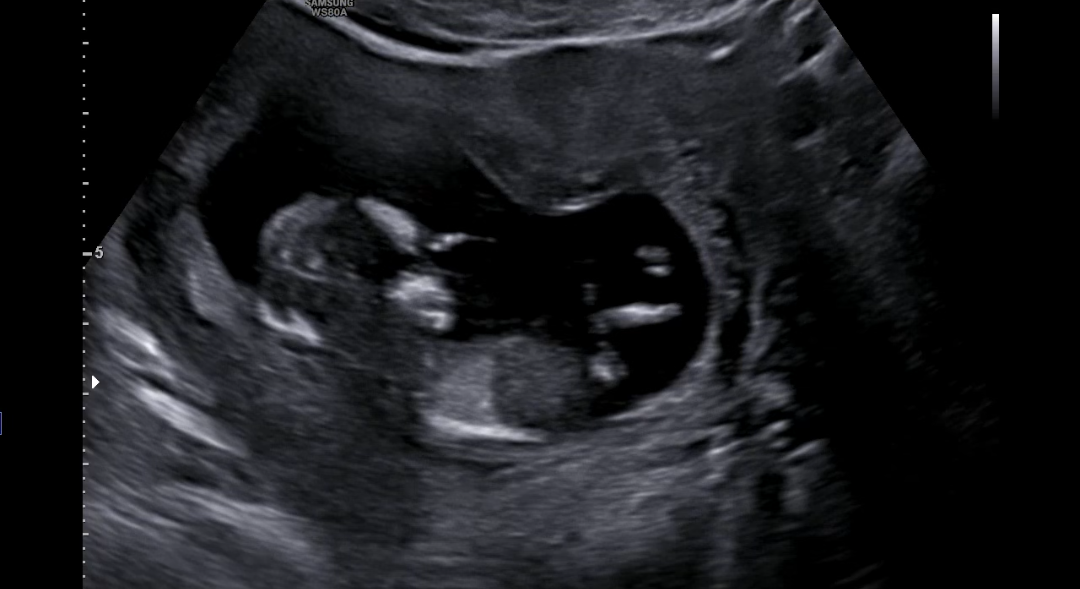

그리고 2층으로 올라가 정밀초음파를 진행했는데요,,! 고은빛은 초음파 봐주시는 선생님이 따로 계시더라구요.

오늘은 첫 정밀초음파다보니, 목투명대도 재야하고, 콧대도 봐야하고,, 했는데 뽀동이가 너무 얌전히 있더라구요ㅠㅠㅎㅎ

열심히 자세도 바꾸고, 기침도 해보며 결국 모두 확인했고 정상,,! 소견 받았습니다ㅎㅎ 다행이야,,

콧대?는 0.18cm, 목투명대는 1.52cm였어요!